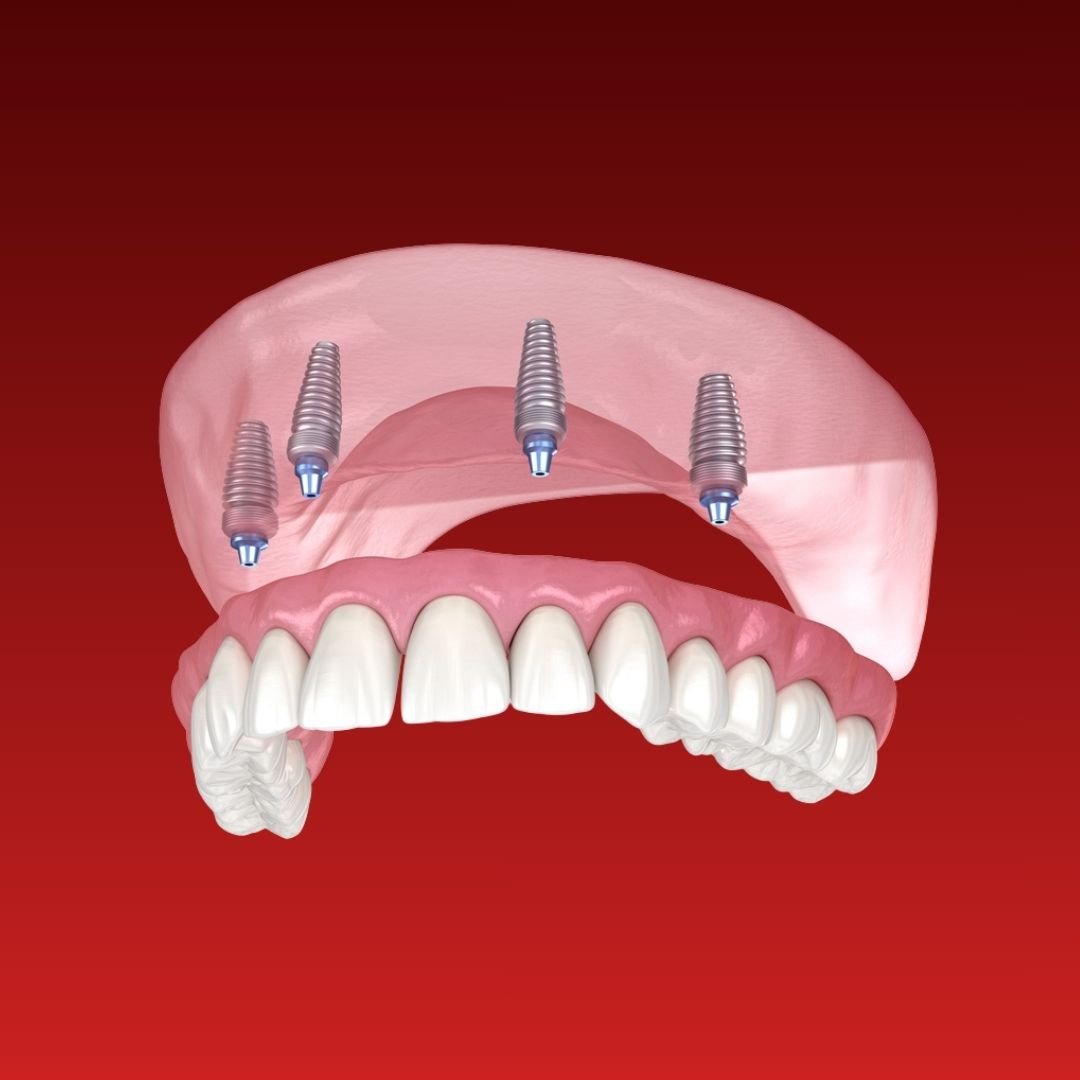

Super Saver All-on-4 Package

- 4 Nobel Biocare Implants

- Final Restoration

- Free Initial Consultation and Post-op Follow up...

All Inclusive All-on-4 Dental Implants Package

- 4 dental implants with abutments

- Final Restoration Fix Hybrid Denture

- Zirconia upgrade - $...

Mega Saver All-on-6 Deal

- All-on-6 implants per jaw

- DIO Implants

- Tomography 3D, intraoral scanning 3D

Mega Saver All-on-4 Deal

- All-on-4 implants per jaw

- DIO Implants

- Tomography 3D, intraoral scanning 3D